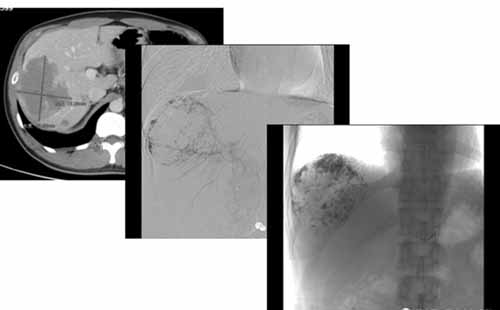

(手術(shù)過程:通過DSA下動脈造影,找到供血動脈,注入栓塞劑進行栓塞。)